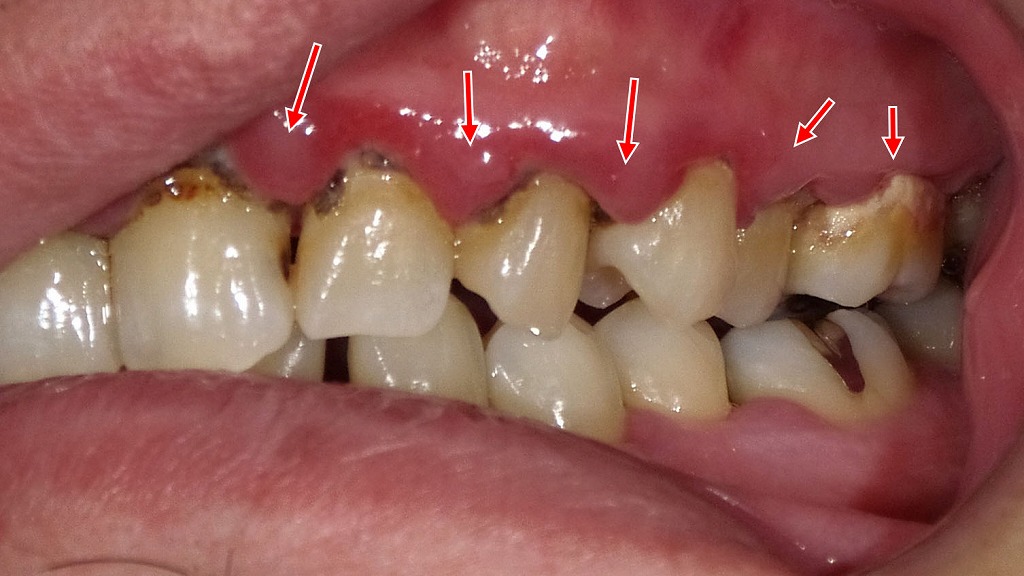

画像では、歯ぐきの腫れや発赤、歯と歯ぐきの境目に付着した歯垢・歯石が確認でき、進行した歯周病の所見がみられます。

歯周病では、歯周ポケット内の細菌が強い臭いのガスを発生させるため、他人が気づくほどの口臭につながることがあります。

セルフケアだけでは改善が難しく、歯科医院での歯周病治療と定期的なクリーニングが重要です。